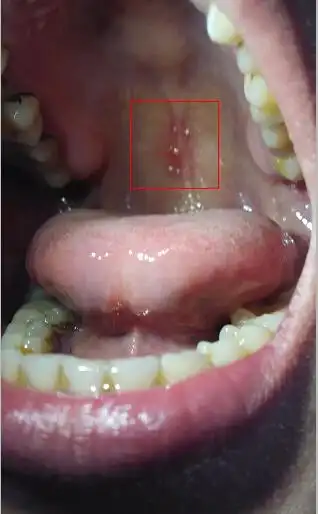

软腭上有小疙瘩图片

最近发现口腔上颚长了个米粒大小的疙瘩,开

大家帮我看看,嘴巴上颚长了小点点,用舌头舔能感觉到,不疼不痒 怎么了